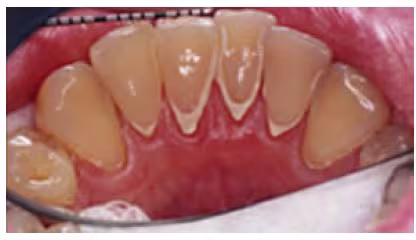

Figure 19. Supragingival calculus